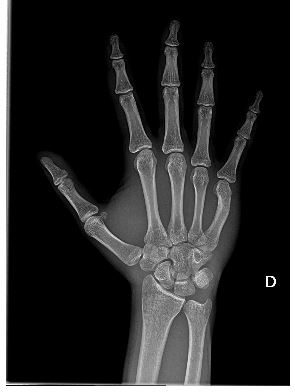

circa 4 mesi fa in un momento di rabbia ho tirato un pugno fortissimo al muro, ho avvertito molto dolore alla mano e nella zona sotto il palmo in prossimità del 5 metacarpo si era annerita, ma riuscendo comunque a muovere la mano non sono andato al pronto soccorso. Di recente ho fatto una radiografia che dice:

Quesito diagnostico: trauma contusivo circa 4 mesi fa, primo accertamento in persistenza di sintomatologia dolorosa v metacarpo a dx.

Non disponibili analoghi precedenti utili per confronto.

Deformazione a concavità destra del 5 metacarpo, a fulcro diafisario distale, di difficile tipizzazione, anche sulla scorta di questo solo esame : possibile esito riparato fratturativo e/o costitutivo, dato da correlare con la clinica.

Nei radiogrammi eseguiti non evidenza di franche alterazioni a focolaio in atto.

Rizoartrosi.

Conservati i rapporti articolari.

Osteopenia, verosimilmente da disuso.

Sesamoide metacarpali al primo dito

Note artrosiche.